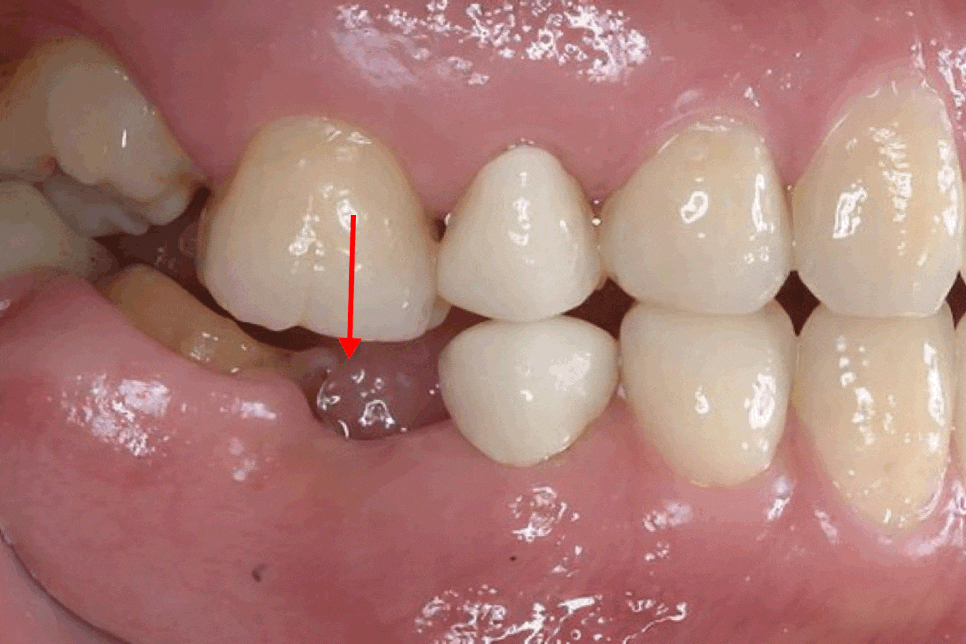

<치조골 흡수>

치아가 존재해야 치조골에

지속적이 자극이 전달되는데

치아가 상실되면 이러한 자극이 사라지면서

해당 부위의 치조골이 점차 줄어듭니다.

시간이 흐를수록 치조골의 양이 감소하면

이후 임플란트를 진행할 때

뼈이식과 같은 추가 처치가 필요할 수 있습니다.